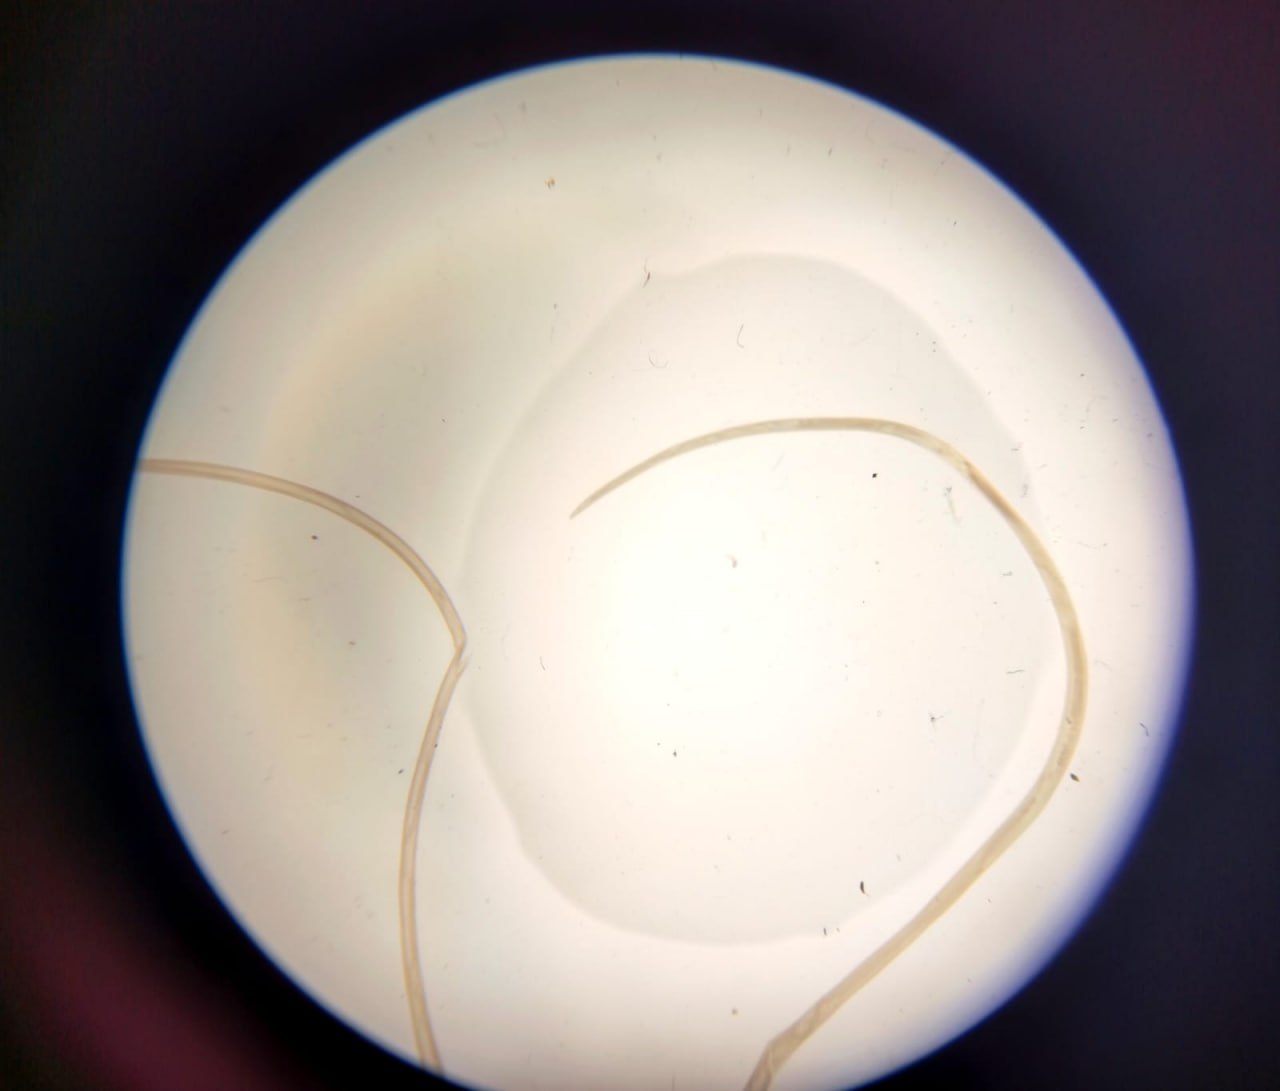

За даними обласного центру контролю та профілактики хвороб МОЗ, жінка звернулася через набряк і болі в області повіки. Під час огляду медики виявили паразита виду Dirofilaria та видалили його хірургічно.

У мешканки Запоріжжя лікарі виявили під шкірою жахливого паразита. Фото: ЦКПХ